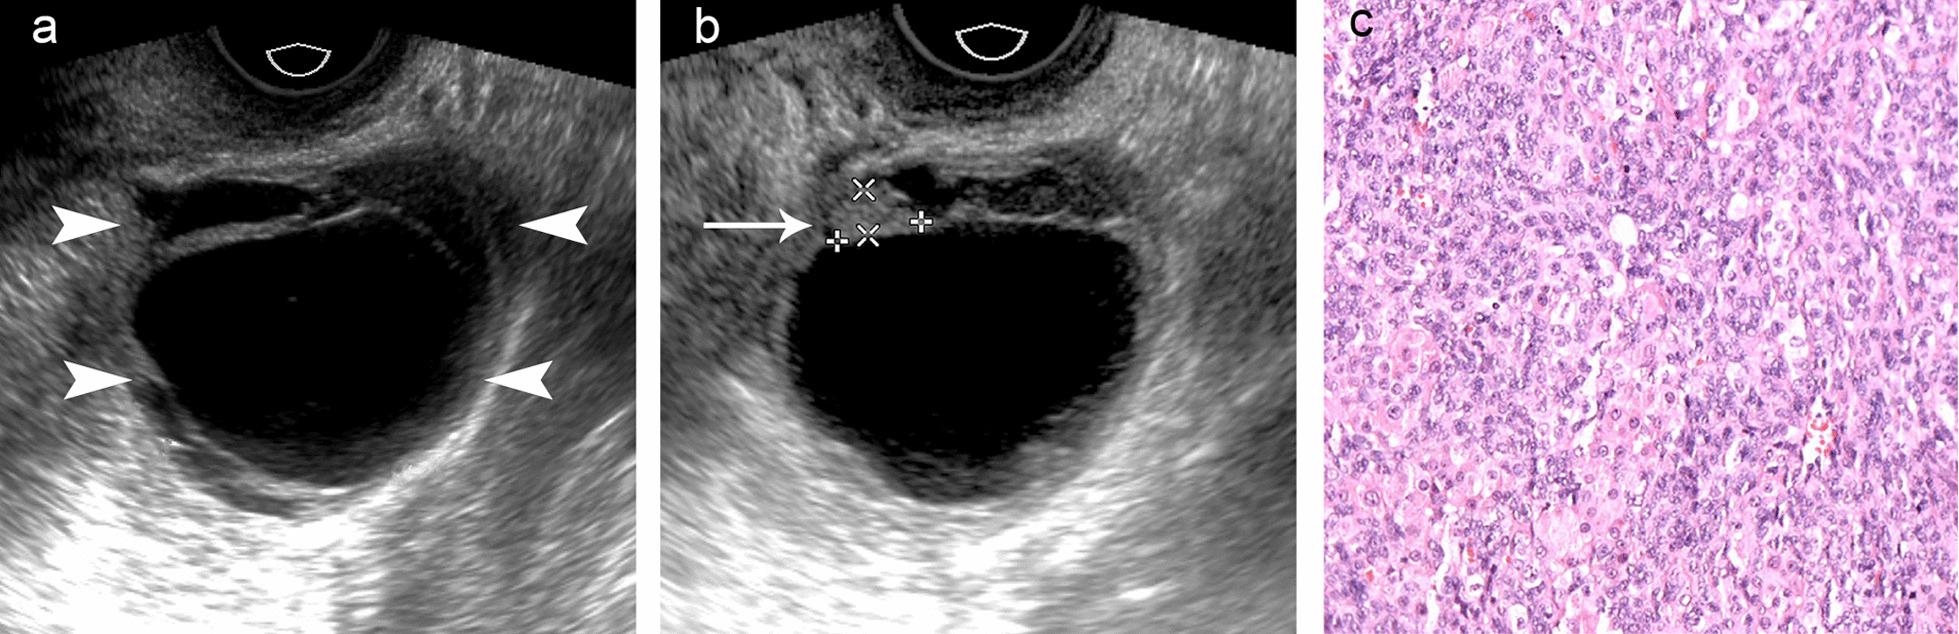

A virilizing ovarian tumor (VOT) is a rare cause of hyperandrogenism in pre- and postmenopausal women. Although transvaginal ultrasound is considered as the first-line imaging method for ovarian tumors, it is examiner-dependent. We aimed to summarize the clinical and ultrasound manifestations of VOTs to help establish the diagnosis with emphasis on those causing diagnostic difficulty.

Patients with VOTs were predominantly premenopausal. All patients showed androgenic manifestations with serum testosterone levels elevated to varying degrees. The tumor size of VOTs was significantly correlated with age (P < 0.001). The VOTs in the postmenopausal group were significantly smaller than those in the premenopausal group (median 1.8 cm [range, 1.3-4.8 cm] vs 4.5 cm [range, 0.7-11.9 cm]; P = 0.018). Twenty-seven out of 31 VOTs were successfully identified by ultrasound. On ultrasound, VOTs are mostly solid and hypoechoic masses with enhanced vascularity. Four VOTs (0.7-1.5 cm) were radiologically negative, and they were the smallest among all patients.

Patients with VOTs showed androgenic manifestations with varying degrees of hyperandrogenemia. Older patients tend to have smaller VOTs. Ultrasound is an effective method for the detection of VOTs. Some VOTs can be very small and difficult to visualize radiologically, especially in postmenopausal patients. Examiners must remain vigilant about very small VOTs on the basis of endocrine symptoms.